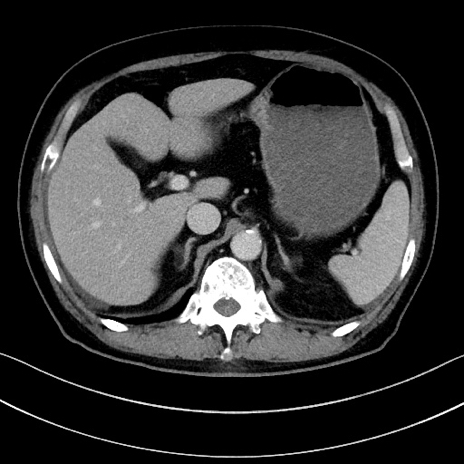

症例15(横断像)

【症例】70歳代男性

【主訴】腹痛

【現病歴】今朝から腹痛あり。全体的に痛い。特に左上の方。排ガスが今日はない。冷や汗が出る。

【既往歴】直腸癌術後

【身体所見】左側腹部〜上腹部に圧痛あり。腹膜刺激症状明らかなではない。軽度反跳痛。左下腹部に術後瘢痕あり。

【データ】WBC 7700、CRP 0.02